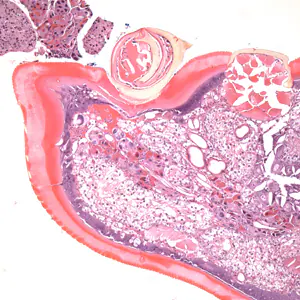

A skin biopsy specimen was collected from the clavicle region of a 45-year-old male who presented with what appeared to be a pigmented lesion. The patient resides in Kentucky and has no known international travel. The biopsy specimen was sent to Pathology for routine histologic work-up. Objects suggestive of an organism were examined on slides stained with hematoxylin-and-eosin (H&E). The attending pathologist captured images and sent them to CDC-DPDx for diagnostic assistance. Figures A–E represent five of the images received. What is your diagnosis? Based on what criteria?

Figure B